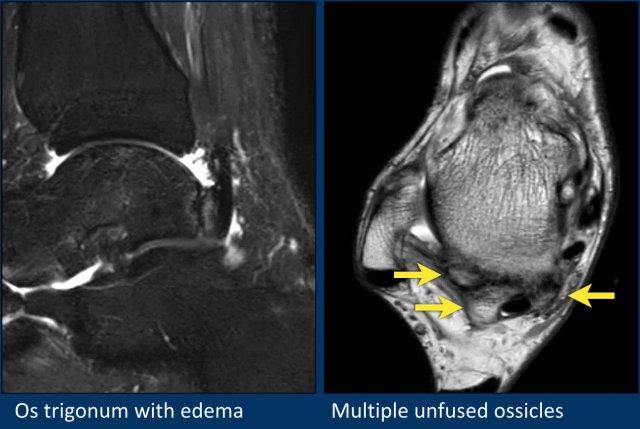

Đây là một ví dụ về os trigonum với phù nề khá kín đáo.

Trường hợp này được trình bày để minh họa sự đa dạng phong phú của các xương phụ và củ xương ở mặt sau xương sên.

Bệnh nhân này có củ bên nổi bật chưa hợp nhất với kết nối dạng sợi (fibrous connection) với xương sên, do đó đây là os trigonum hợp nhất một phần.

Trên ảnh cắt ngang (axial), có thể thấy thêm các củ xương nổi bật chưa hợp nhất ở cả mặt trong và mặt ngoài của củ bên.